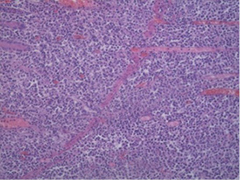

The macroscopic histopathology analysis revealed the presence of a tumor with dimensions of 6x5x2.5 cm (ulcerative type) that spreads in the surrounding adipose tissue. The microscopic aspect of hematoxylin and eosin staining presented with infiltrative growth of lymphoid cells with large nuclei and frequent mitoses. Immunohistochemical staining showed high proliferation over 90% of Ki67 and CD20 (Figures 3a, 3b, and 3c). The overall pathology report concluded the presence of aggressive diffuse large B-cell lymphoma.

3a

3b

3c

Figure 3. 3a – Hematoxylin Eosin stain with infiltrative growth of Lymphocytes, 3b – Ki67 stain with high proliferation, 3c – CD20 stain with proliferation over 90% (100x magnification)